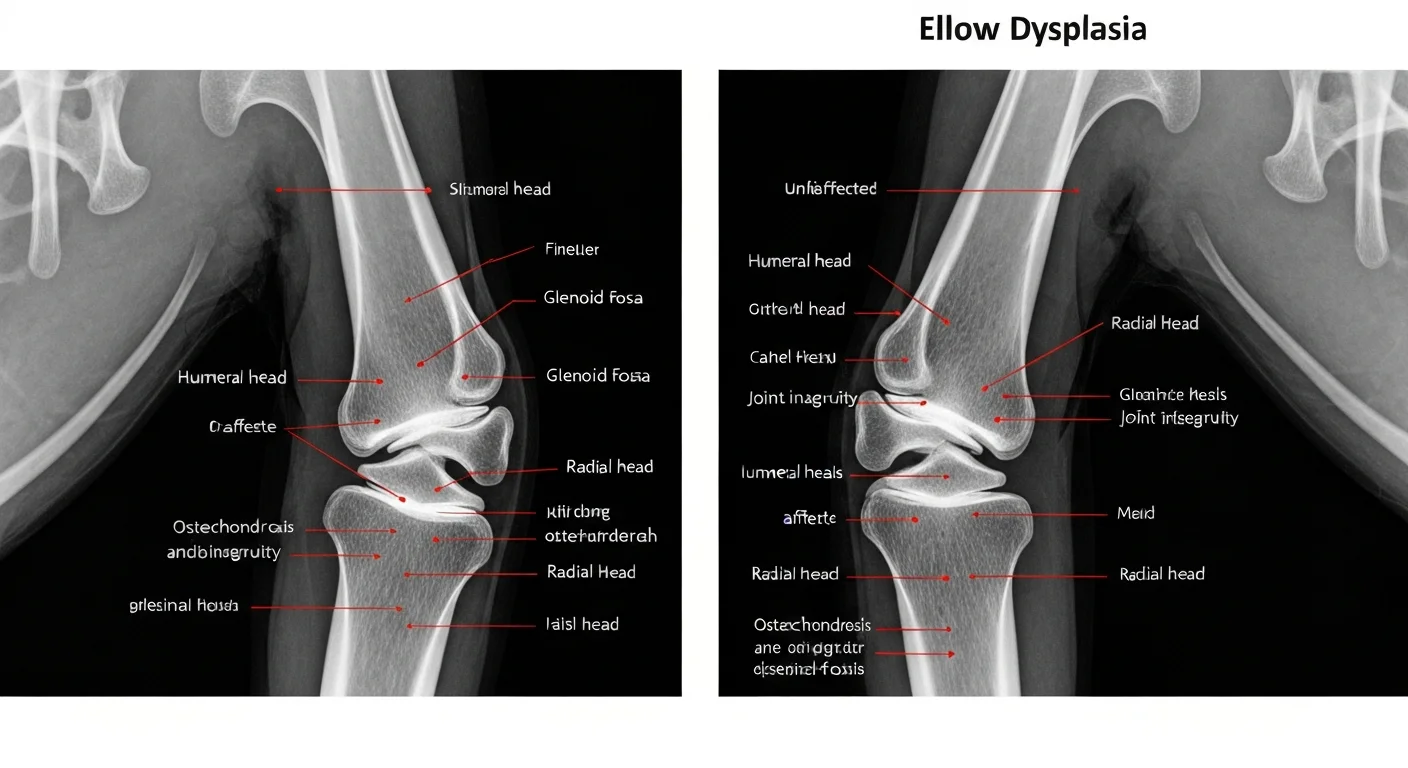

Radiographic findings frequently differ between elbows in bilateral disease. One elbow may show frank FCP with obvious osteophytosis while the contralateral shows only subtle subchondral sclerosis of the ulnar notch, an early radiographic indicator that can easily be dismissed as normal variation. This asymmetric severity pattern argues for high radiographic sensitivity thresholds when evaluating the "less affected" elbow in dogs with confirmed unilateral disease. CT scanning of both elbows under the same anaesthetic provides superior sensitivity for bilateral disease detection and is increasingly the standard at referral centers.

Radiograph showing bilateral elbow dysplasia comparison in large breed dog